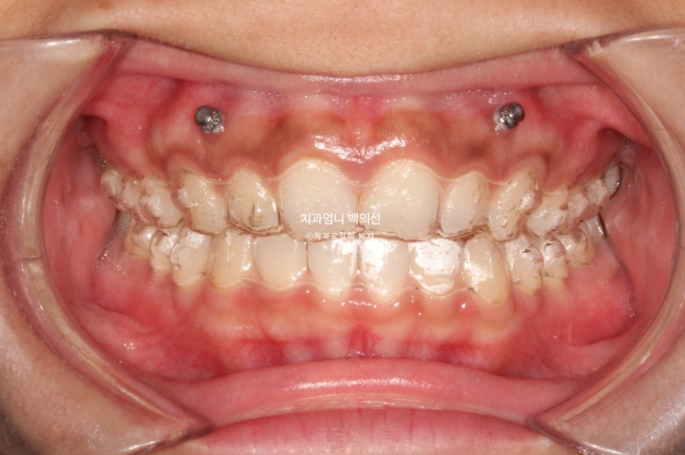

어금니 교합이 좋아 인비절라인 라이트 권유드렸고, 대신 미니스크류를 심고 고무줄을 걸어 길지 않은 기간에 과개교합과 거미스마일을 확실히 개선하기로 했습니다.

24.07

첫세트부터 앞니쪽에 교정용 나사를 심고 고무줄을 겁니다.

24년 7월까지, 첫 세트의 14개 장치를 모두 낀 후 모습입니다.

과개교합이 해소되며 아래앞니가 비로소 모습을 드러냅니다.

벌어진 틈을 깔끔하게 사라졌습니다.

삐뚤했던 앞니배열도 좋아졌습니다.

3.5개월의 변화라고 보기 힘들정도로 환자분은 열심히 껴주었고 치료계획도 완벽했습니다.